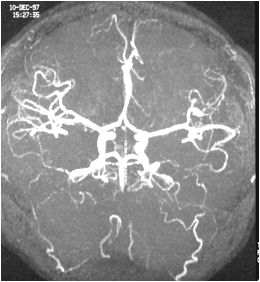

脑的动脉来源有颈内动脉和椎—基底动脉系

以顶枕沟为界,大脑半球前2/3和部分间脑由颈内动脉供应;大脑半球后1/3及部分间脑、脑干和小脑由椎—基底动脉系供应。

颈内动脉发出大脑前动脉、大脑中动脉和脉络丛前动脉等,大脑前、中动脉均分为皮质支和中央支,其中央支供应基底核及内囊,尤其是大脑中动脉的中央支易破裂引起脑溢血,从而导致“三偏综合症”。

基底动脉发出大脑后动脉等。

由大脑前动脉、前交通动脉、颈内动脉末端、大脑后动脉和后交通动脉共同构成大脑动脉环(Willis环),异常情况下以维持脑的血液供应。